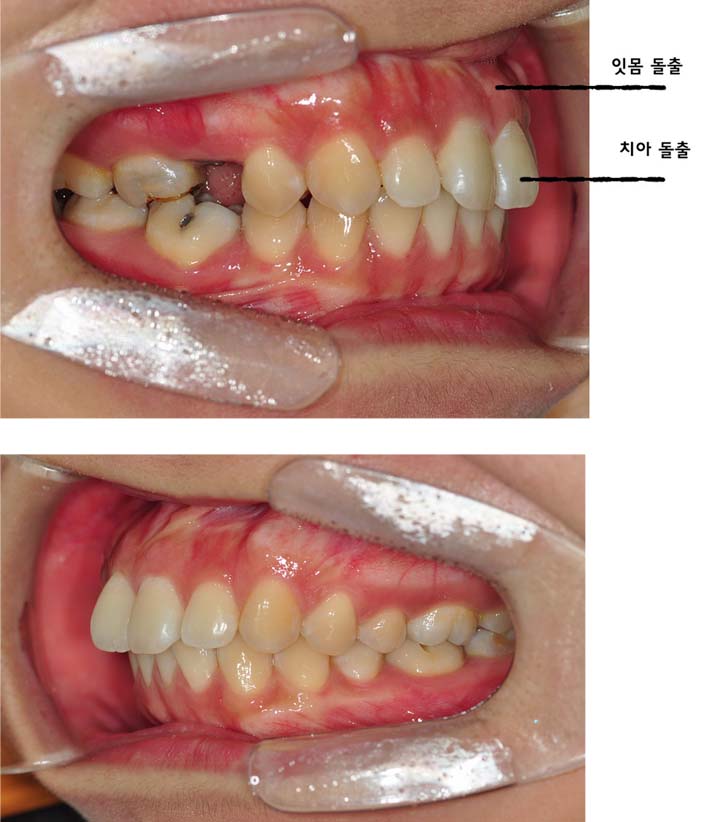

저는 치아가 덧니는 심하지 않기때문에 교정하기에 어렵지 않을거라 혼자 생각했는데 제가 잇몸과 치아 모두 돌출되어있고 어려운 케이스라고 하시더라구요 헝헝 (아래 사진을 참고해주세요~)